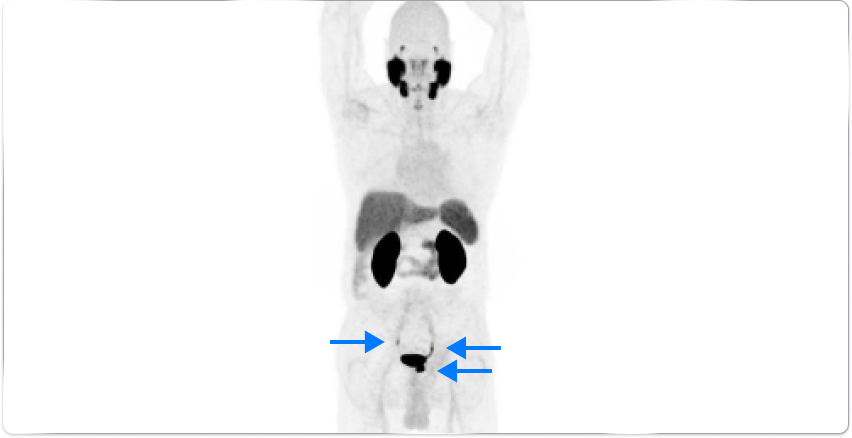

High-risk patient with newly diagnosed prostate cancer

Age

63

PSA (ng/mL)

26

Gleason Score

4 + 3

PYLARIFY may have helped prevent overtreatment